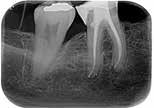

Fase diagnostica, che prevede una prima anamnesi clinica, una radiografia pre-operatoria per interpretare l’anatomia endodontica, al fine di definire un corretto piano di trattamento.

La diagnosi in endodonzia non può prescindere dall’esecuzione di esami radiologici accurati, in grado di mostrare l’esatta anatomia delle strutture dentali, in particolare dell’anatomia radicolare e dei tessuti di supporto.

Le apparecchiature radiologiche convenzionali (endorali) forniscono una rappresentazione bidimensionale di strutture anatomiche tridimensionali.

Questa immagine “appiattita” può nascondere, sovrapponendole, alcune aree anatomiche, soprattutto quelle in senso bucco-vestibolare (spessore dei tessuti).

Anche adottando tecniche radiografiche in grado di migliorare la qualità dell’immagine (tecnica del cono lungo con centratore “tipo Rinn”, proiezione dei raggi con inclinazione mesio-distale), i limiti tecnologici imposti dagli apparecchi endorali non sempre sono superabili.